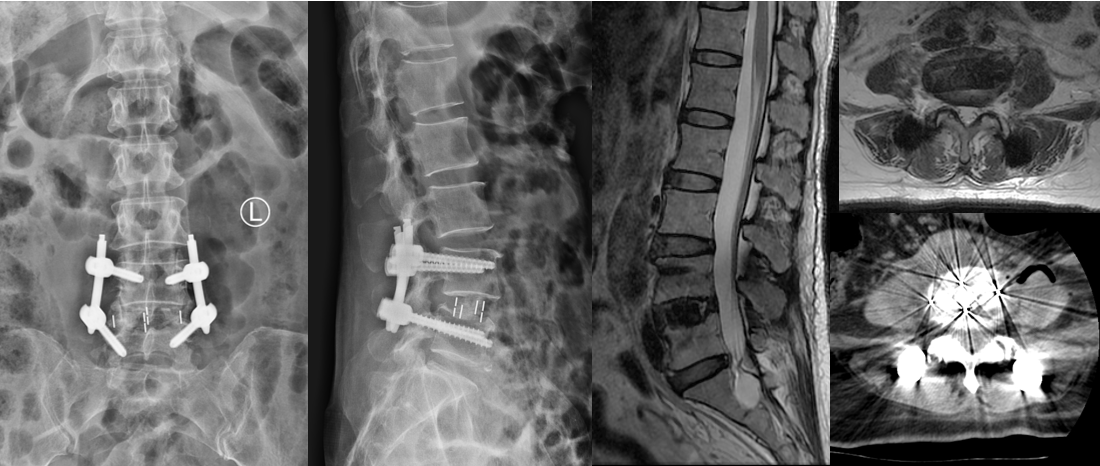

第二例患者男性,67岁,患者因“腰痛并右下肢放射痛1年余,加重1月”入院,发病以来反复保守治疗,未好转,1月前症状加重,间歇性跛行,行走100米后因疼痛无法继续行走。入院后经术前讨论、评估,制定治疗方案,行OLIF手术。次日患者下地活动,下肢症状消失,疗效满意。

术前影像

术中

术后复查